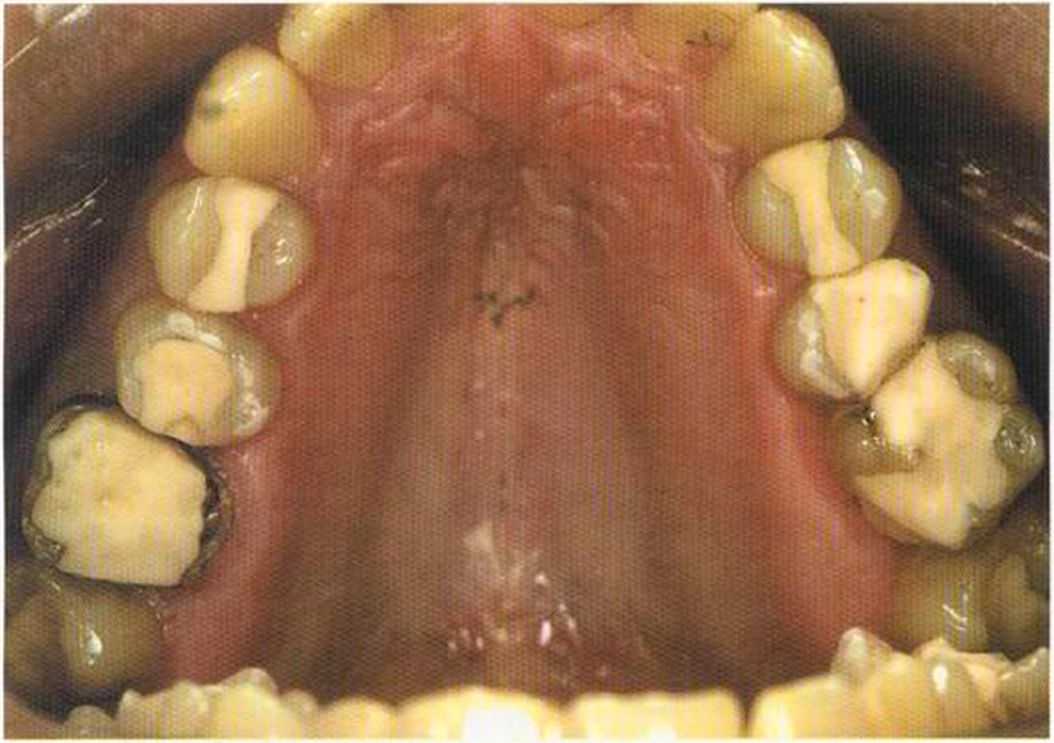

Этому пациенту были изготовлены керамические вкладки в области боковой группы зубов и коронки 1п-Сегат. Перед лечением удалены старые пломбы из амальгамы, снят размягченный дентин.

Сначала зубы, на которые будут изготовлены керамические вкладки, были отпрепарированы и подготовлены под коронки 1п-Сегат.

Только что зацементированная работа в полости рта. Цементирование керамических вкладок осуществлено на цемент двойного отверждения Vivadent, а коронок ln-Сегат на Panavia ТС.

Здесь были установлены керамические, послойно нанесенные вкладки. Они выглядят более живыми по сравнению с прессованными.